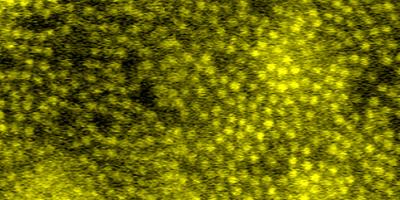

neuron vessels

Inner retinal capillaries (top) and choriocapillaris (bottom) imaged in a living human eye using multimodal adaptive optics enhanced indocyanine green angiography.

Read the associated publication.

View the video: A look at the smallest blood vessels in the eye